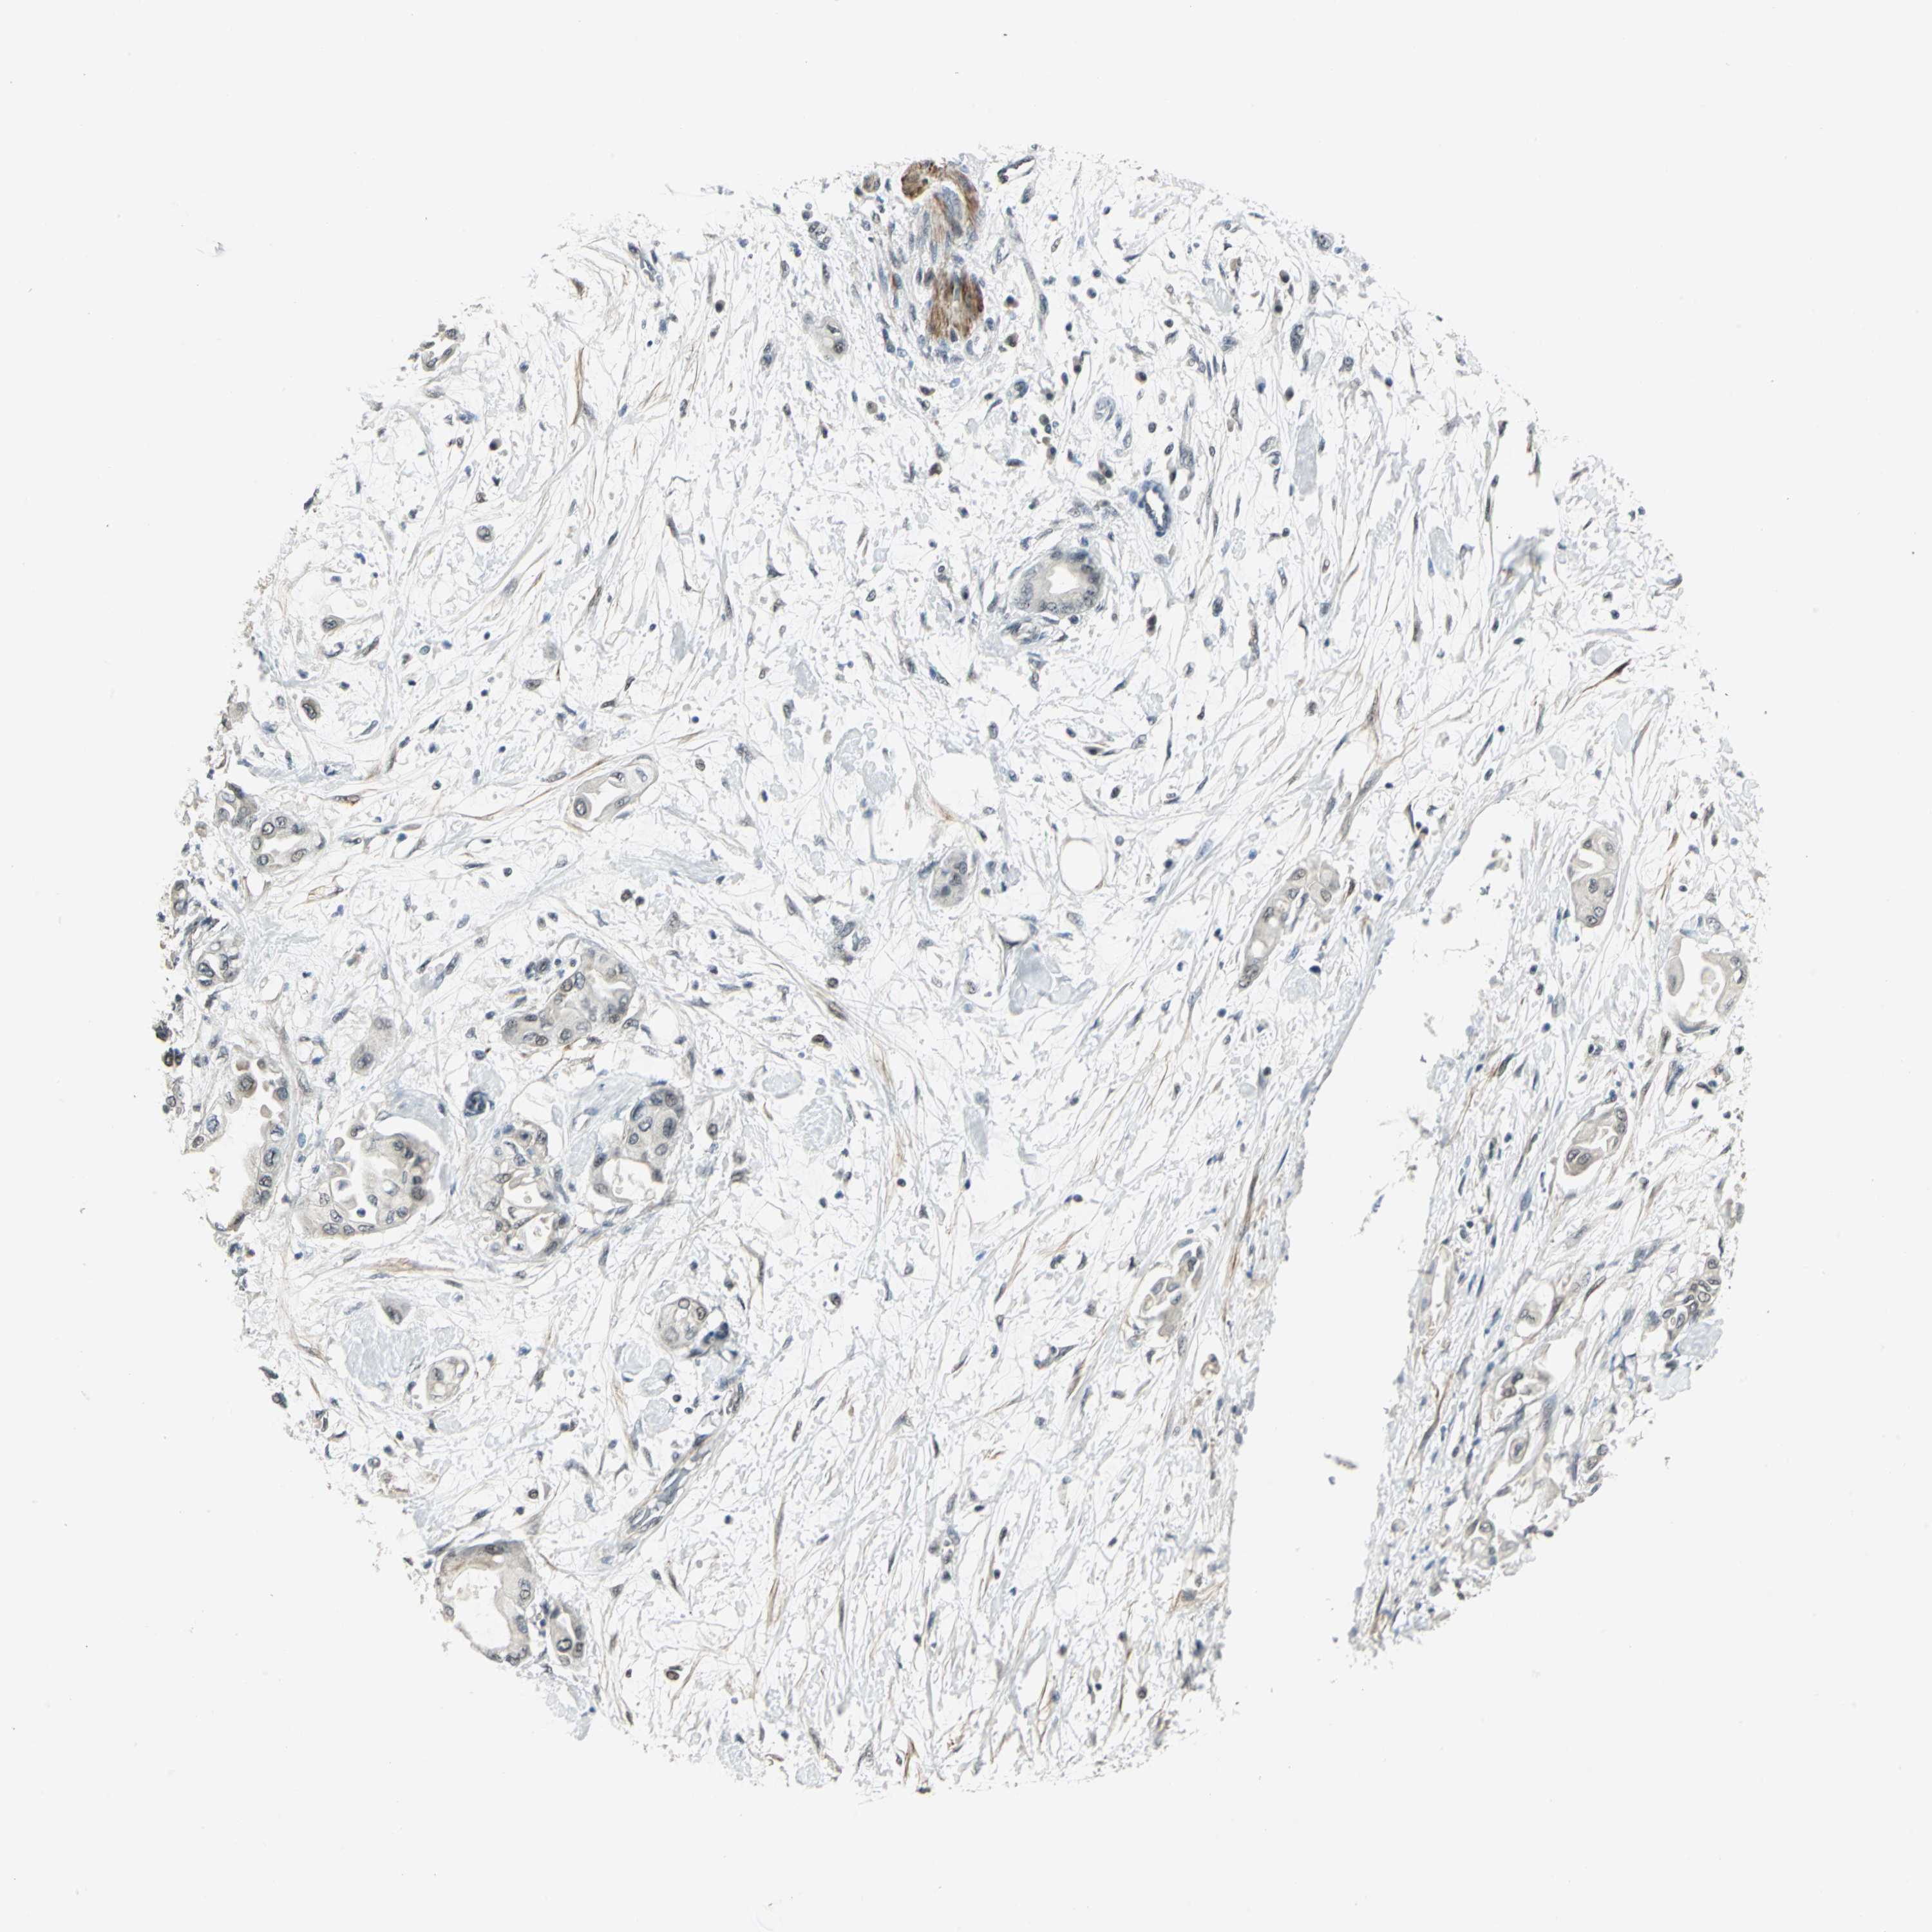

PANCREATIC CANCER - Protein expressioni

A mouse-over function shows sample information and annotation data. Click on an image to view it in a full screen mode. Samples can be filtered based on level of antibody staining by selecting one or several of the following categories: high, medium, low and not detected. The assay and annotation is described here.

Note that samples used for immunohistochemistry by the Human Protein Atlas do not correspond to samples in the TCGA dataset.

Antibody stainingi

Antibody staining in the annotated cell types in the current human tissue is reported as not detected, low, medium, or high, based on conventional immunohistochemistry profiling in selected tissues. This score is based on the combination of the staining intensity and fraction of stained cells.

Each image is clickable and will lead to virtual microscopy that enables deeper exploration of all samples and also displays staining intensity scores, fraction scores and subcellular localization as well as patient and tissue information for each sample.

Antibody HPA005544

Antibody CAB004508

Staining

High

Medium

Low

Not detected

Intensity

Strong

Moderate

Weak

Negative

Quantity

>75%

75%-25%

<25%

None

Location

Nuclear

Cytoplasmic/membranous

Cytoplasmic/membranous,nuclear

Adenocarcinoma, metastatic, NOS